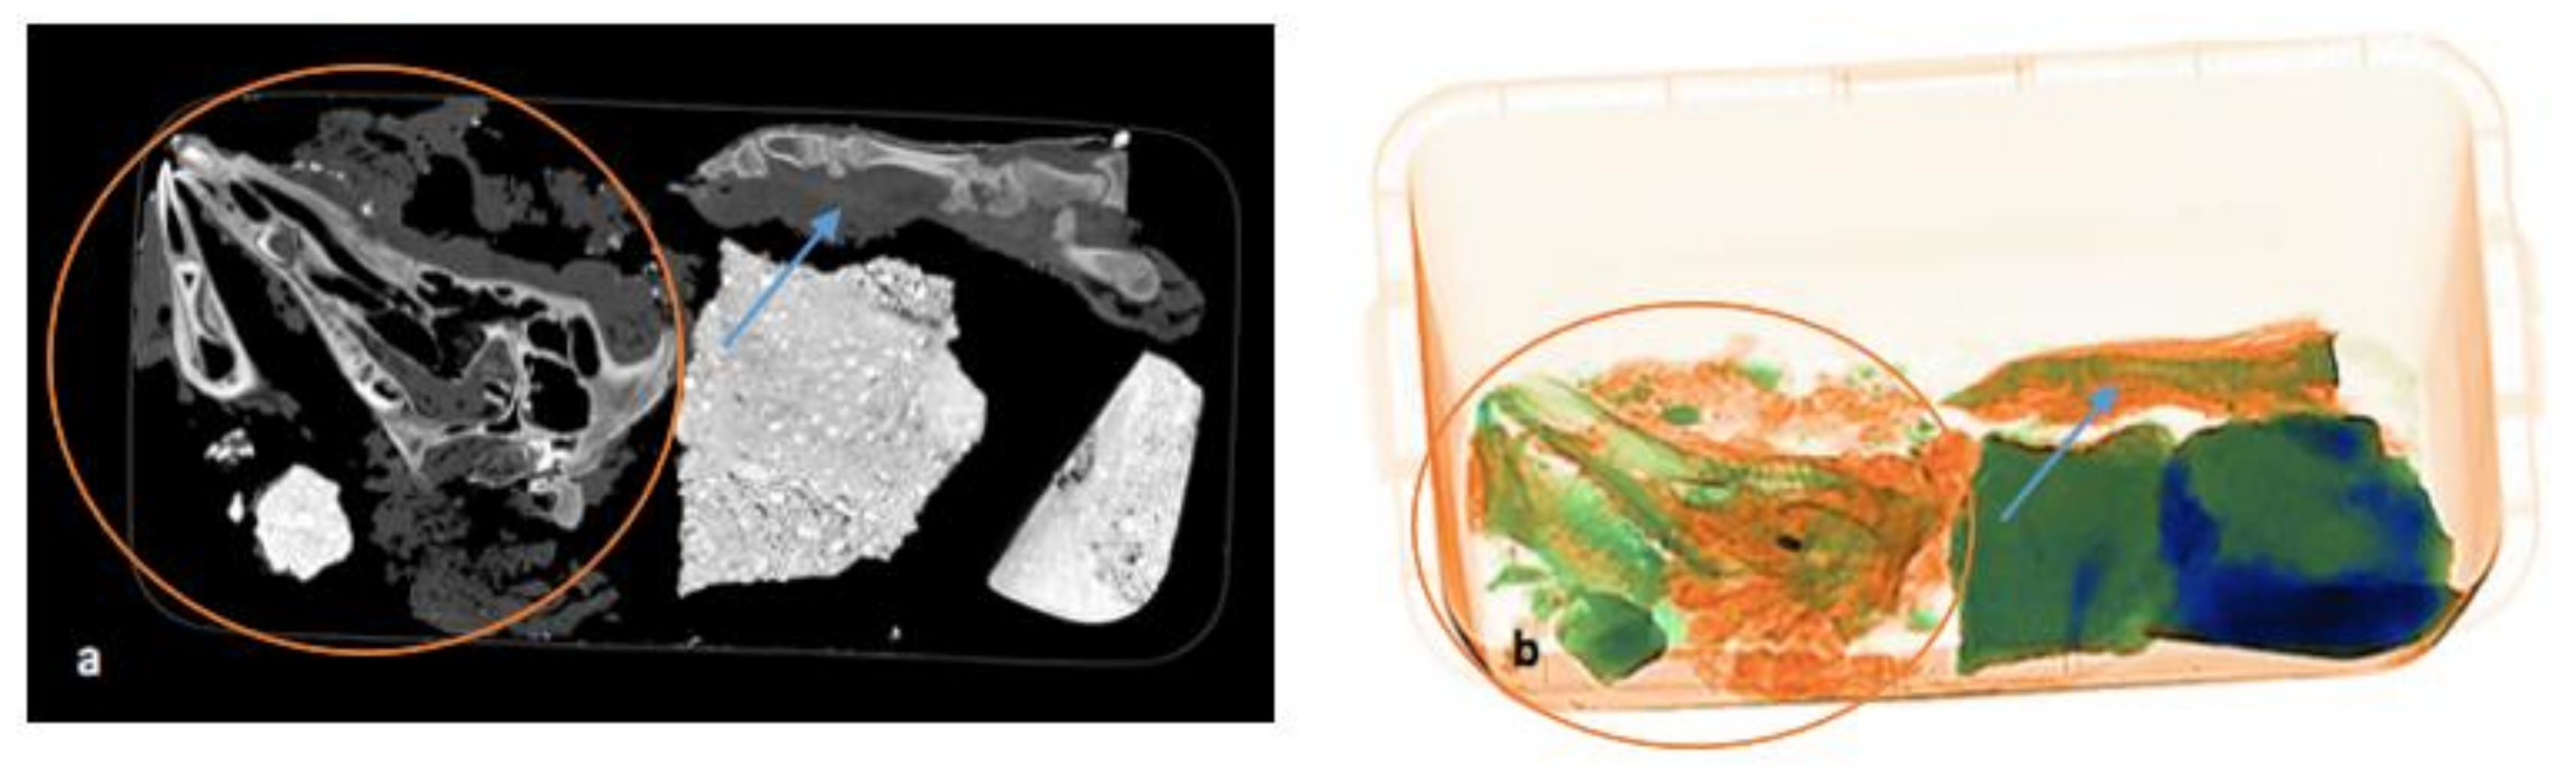

A human torso was found at the described location. During a later search for the remaining body parts, several concrete blocks were found in a stream behind the farm. As the specialists suspected that they might hold the missing parts, the blocks were scanned with a mobile X-ray machine of the Hamburg customs department.

With the help of this mobile X-ray device, the body parts could already be localized in the concrete on site (original image; Figure 1). Those X-ray images helped to carefully remove the remains with a percussion drill, hammer, and chisel. The remains were then taken to the Institute of Legal Medicine in Hamburg, where a pmCT and an autopsy of all body parts were carried out with subsequent DNA and toxicological examinations [23].

Figure 1.

Position of the victim’s head (a) and thigh (b) in the concrete. Two roundish defects and possibly projectiles in the skull are visible and marked with arrows (picture provided by Hamburg customs department [23]).

On the final pmCT/ X-ray image in Figure 7a,b, the paw is still intact, with bones and soft tissues around it. The bones of the head are disarticulated due to the disintegration of the soft tissue. The projectile is still visible in the orbit.

Figure 7.

(a,b) Comparison of pmCT (a) and X-ray image (b) on 14 September 2021 during the last scan. The disarticulation of the bones and disintegration of soft tissue (red circle) of the head and intactness of the paw (blue arrow) can be seen.